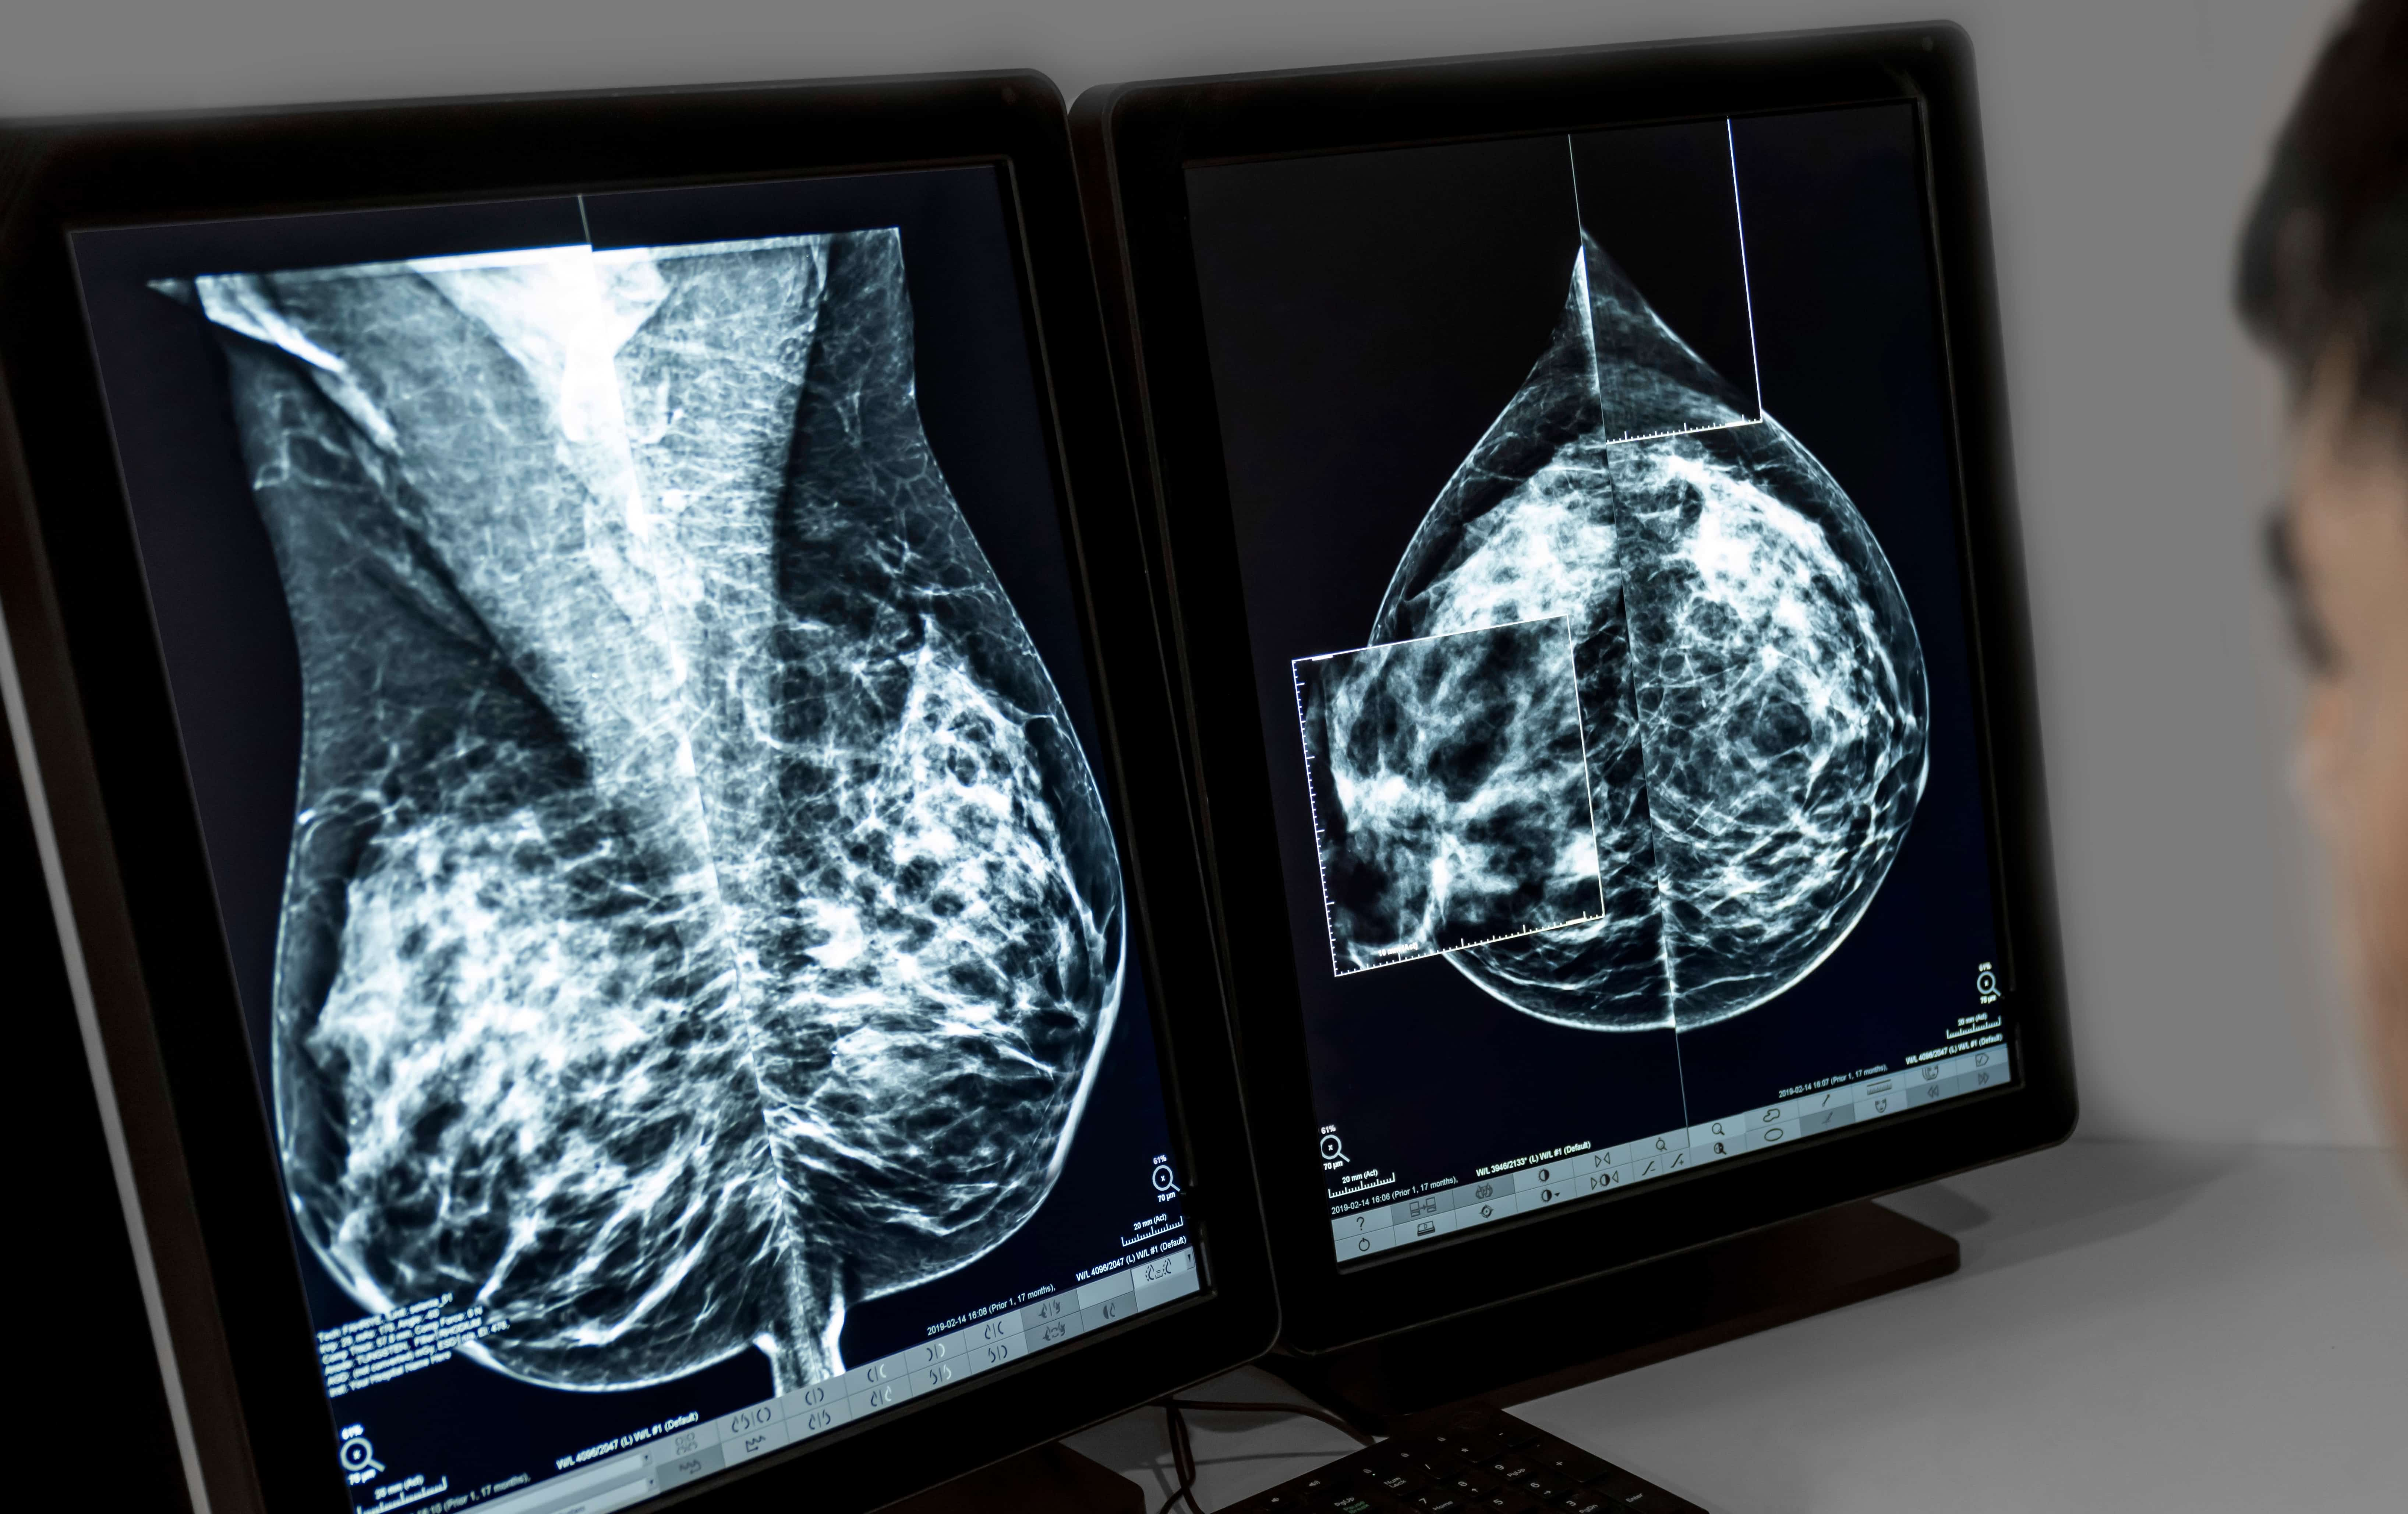

Mammography

What is a Mammogram?

A mammogram is a non-invasive high resolution low-energy digital x-ray picture that plays an essential role in the early detection and screening of breast cancer. Also called mastography, the goal of a mammography is to detect the characteristics of masses or microcalcifications.

During

The images are taken in an upright position with one breast at a time being placed between two x-ray plates. The plates are gradually positioned to compress breast tissue which ensures the best quality image. Once in place, two images are taken of each breast. One image is taken from top to bottom and the other is from side to side.

The images will be interpreted by a radiologist who will share the results with your referring doctor. It is suggested to schedule a follow-up appointment with your doctor to ensure that a clear explanation of the results is provided.